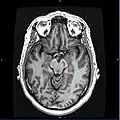

![]() Section through superior colliculus showing substantia nigra. | |

Horizontal MRI (T1 weighted) slice with highlighting indicating location of the substantia nigra. -